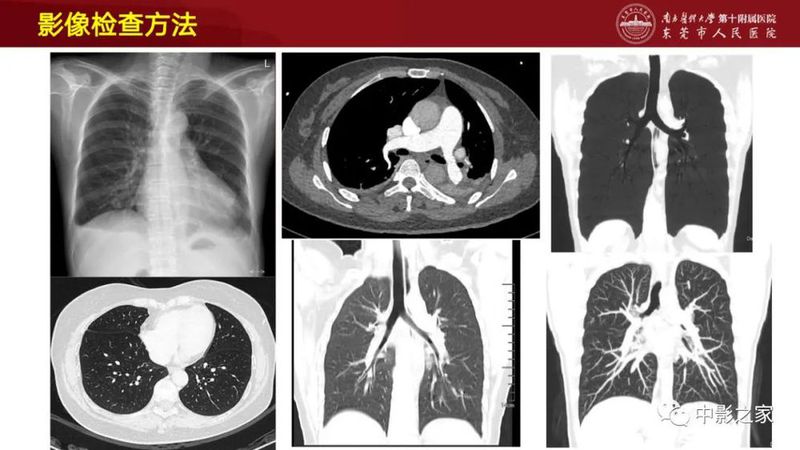

结缔组织相关间质性肺疾病(CTD-ILD)很难,这篇说清楚了!